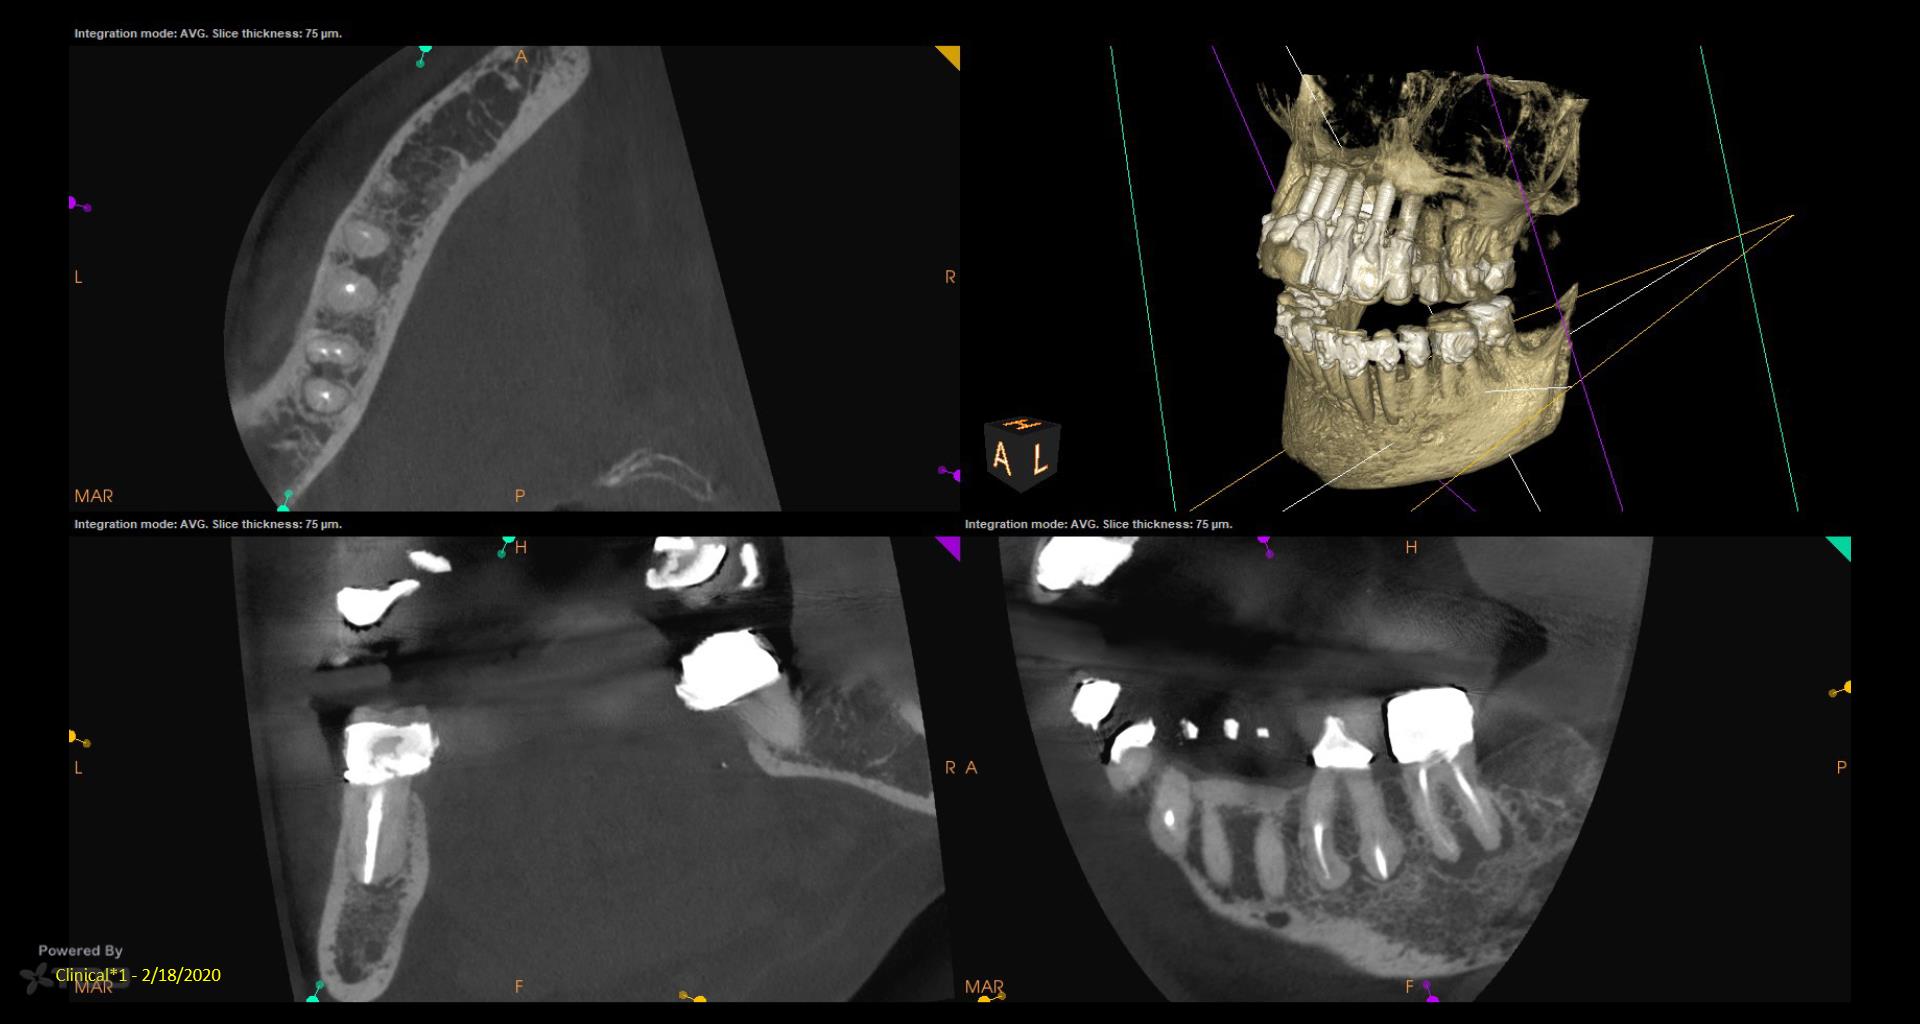

I did a retreat #19 15 years ago. Today symptom free but #18 looks suspicious and maybe even #19……. Perfect case for monitoring….not anxious to do another retreat… gbc

My experience with retreat #19 fifteen years ago was transformative, and I’m grateful to be symptom-free today. However, I’ve noticed convalescent hospital some concerning signs with #18 and possibly #19, which makes me cautious. While I appreciate the value of retreats, I’m not eager to dive back in just yet. Monitoring feels essential now.